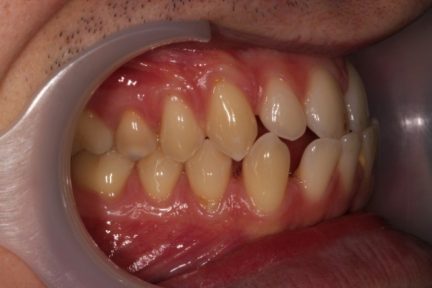

Classe III, articulé croisé antérieur, béance, espacement, diastème

Élastiques : Classe III, nivellement de la courbe de Spee, ingression, expansion, rétraction, réduction interproximale

État initial